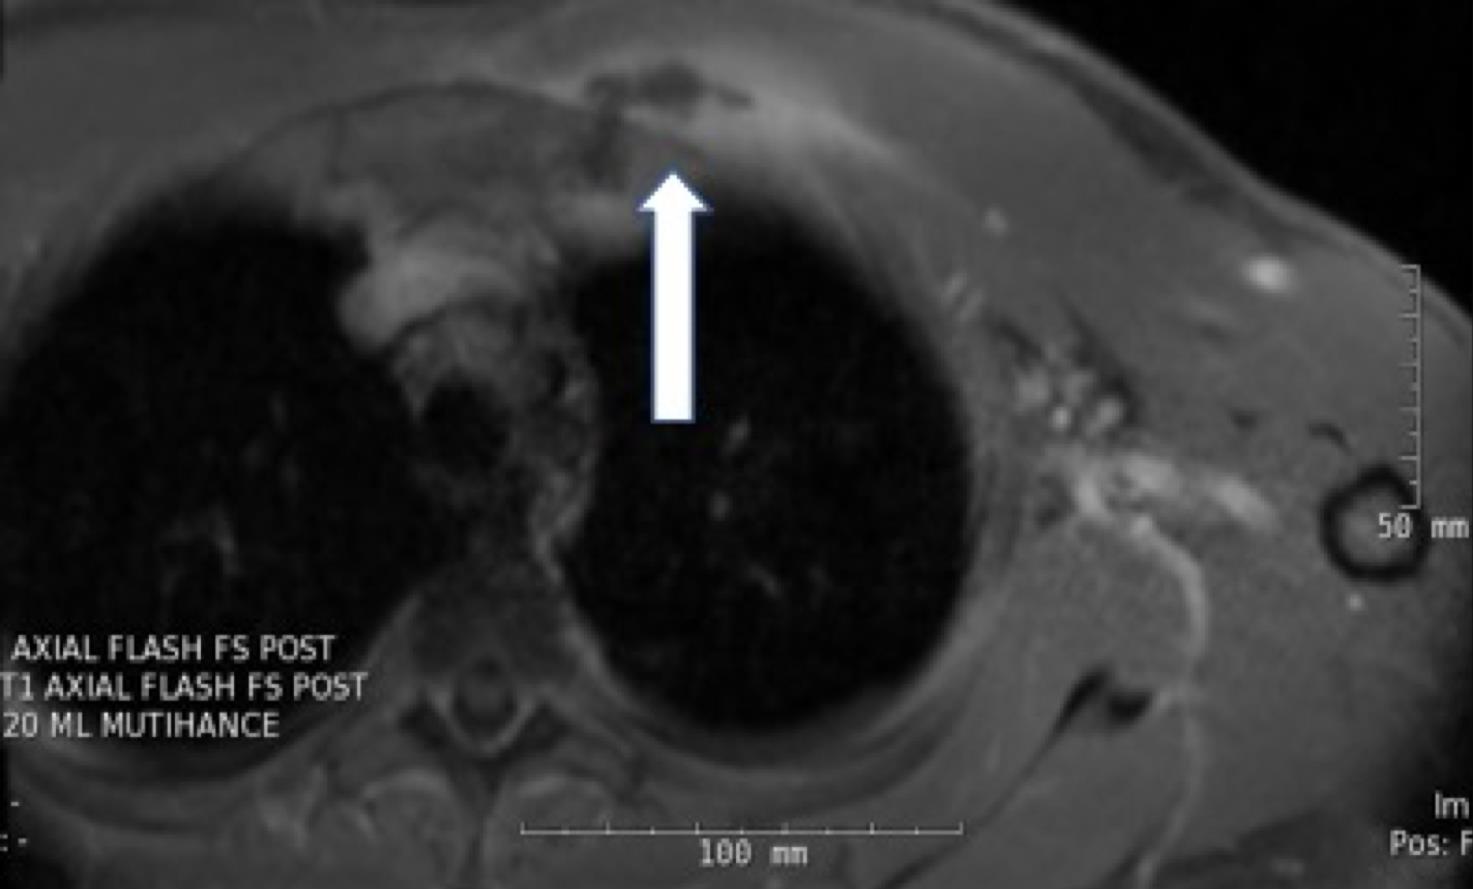

On hospital day 4, magnetic resonance imaging (MRI) of the chest revealed a 3.8 × 1.1 × 1.7-cm fluid collection located inferior to the left pectoralis major muscle extending to the first sternochondral junction (Figures 1 and 2).

Figures 1 and 2. Chest MRI showing a fluid collection.